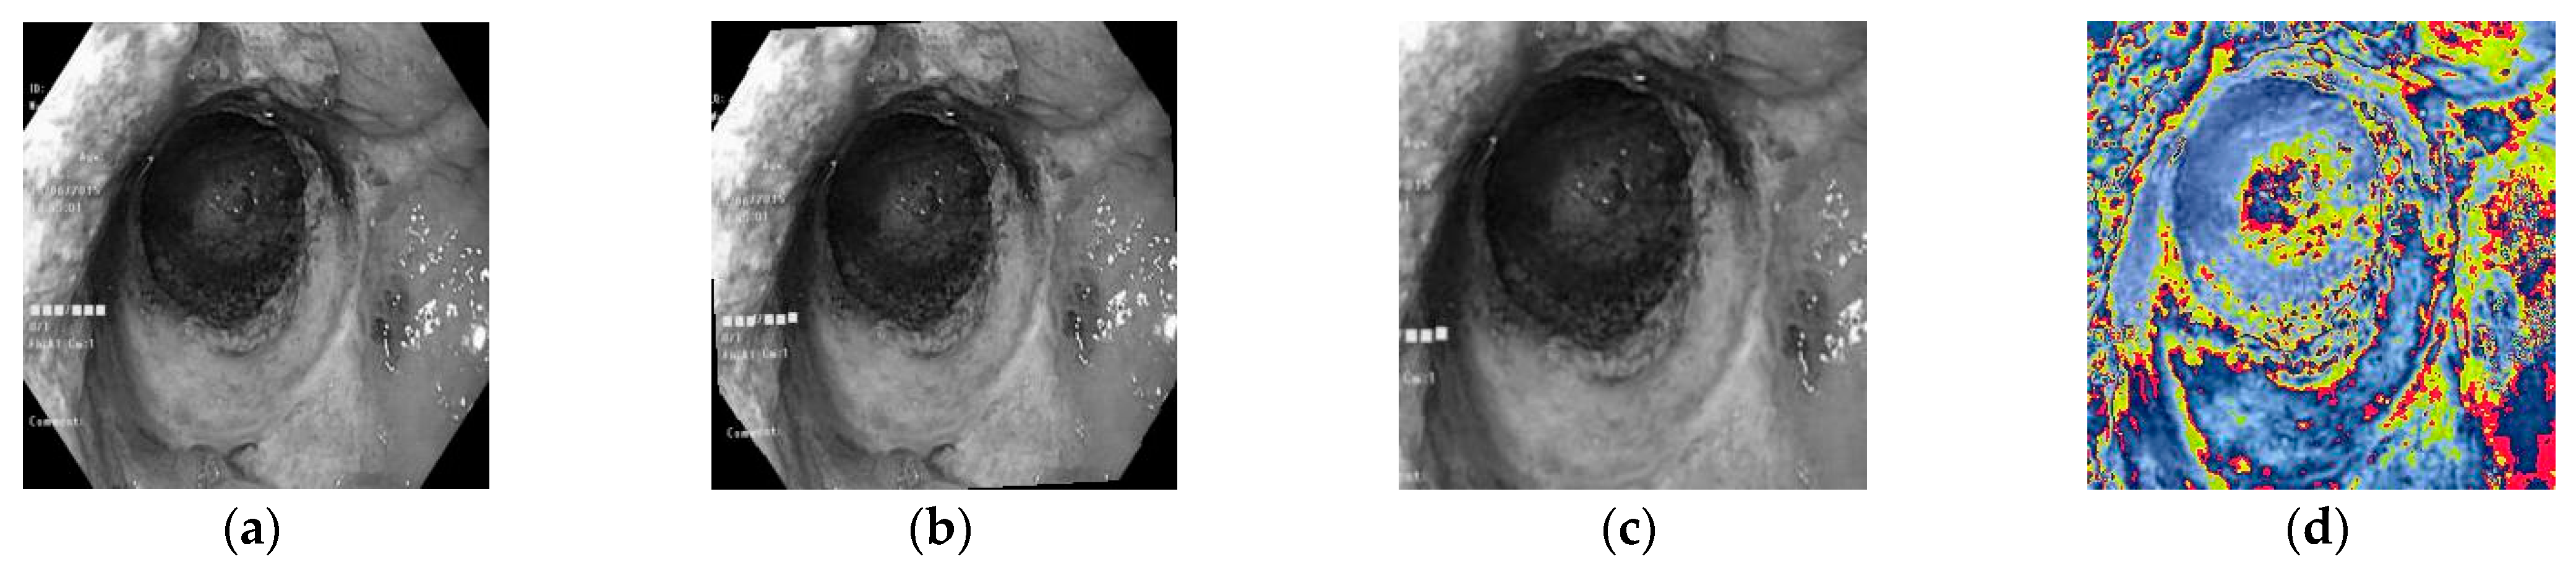

4.3.2. Application of RMA Algorithm on Gastroenterology Dataset

- Liu, L.; Lin, J.; Zhu, S.; Gao, J.; Liu, X.; Xu, C.; Zhu, J. ResNet-based interpretable computer vision model in the endoscopic evaluation of internal hemorrhoids. Mod. Dig. Interv. Diagn. Treat. 2023, 28, 972–975+980. [Google Scholar]